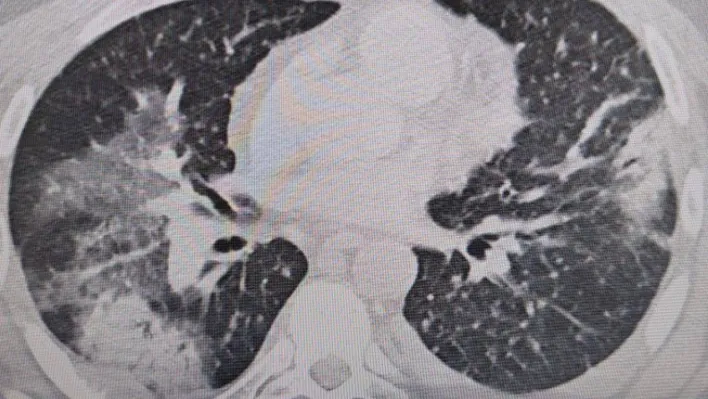

Prof. Dr. Şevket Özkaya, “Legionella” bakterisinin klima sularında üremesiyle insanların yaz zatürresine yakalandıklarını ve kış aylarına göre çok daha fazla vakayla karşılaştıkları bilgisini verdi. Klima zatürresinin özellikle kronik rahatsızlığı olanlarda ölümcül olabileceğini belirten Prof. Dr. Şevket Özkaya önemli uyarılarda bulundu. Özkaya, “Klimaların havalandırılmasıyla beraber insanlar ’lejyoner’ bakterilerini akciğerlerine aldığında ’klima pnömonisi’ ya da ’yaz zatürresi’ dediğimiz hastalığa yakalanıyorlar. Bunun özellikle kronik astım, KOAH ve kanser hastalarında ölümcül sonuçlar doğurabileceğini biliyoruz” dedi.